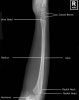

7. Forearm Lateral view(bent/straight arm)